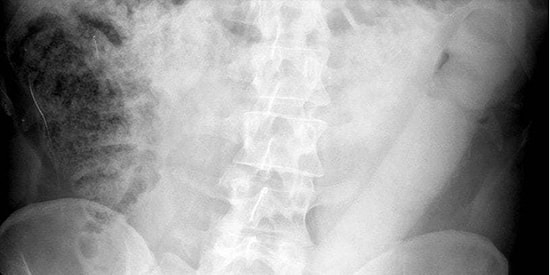

Rektumunda Bulunan 60 Santimetrelik Yapay Penisle Bir Günün Sonunda Hastanelik Oldu!

etiket

Tıp uzmanları, insanların rektumlarından büyük nesneler çıkarmakta oldukça beceriklidirler. Düzinelerce vaka ve binlerce idare birimi dosyası, insanların vücutlarına nesne yerleştirmede sınır tanımadıklarını kanıtlıyor. Durumu düzeltmek ise acil servis elemanlarına ve sindirim sistemi uzmanlarına kalıyor. Zaman geçtikçe bu konuda ortaya çıkan vakaların sayısı arttığı için çıkarma işlemi için uygulanan teknikler de gelişmiş.İtalyan doktorların bu konuda yeni bir teknik bulmalarını sağlayan, vücudundaki upuzun yapay penis ile hastaneye gelen adama uygulanan cisim çıkarma işlemini IFLscience'dan sizler için derledik.